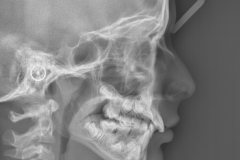

• teleradiografie